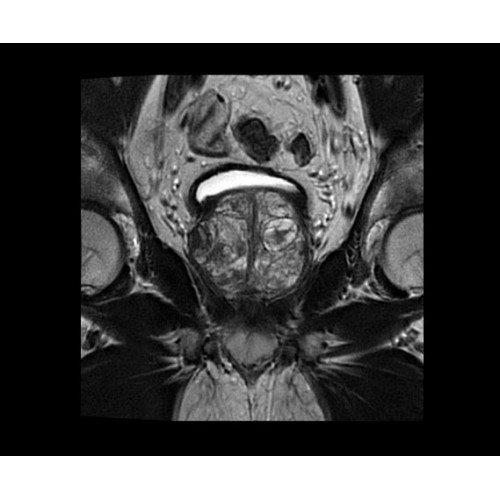

SIGNA PET/MR 3.0T — это гибридная система, в которой совмещаются две принципиально разные технологии — магнитно-резонансную томографию (МРТ) и позитронно-эмиссионную томографию (ПЭТ). Система отличающийся высокой чувствительностью и эффективностью и предназначена для диагностики в области онкологии, неврологии, кардио-васкулярных исследований, исследований воспалительных процессов.

Компания GE Healthcare представляет революционную, полностью интегрированную систему SIGNA PET/MR1, в которой сочетаются времяпролетная технология (TOF) и возможности напряженности магнитного поля 3.0 Тл. Мы поможем вам поднять исследования на более высокий уровень. SIGNA PET/MR позволяет достичь впечатляющей точности и скорости исследований, а благодаря новейшей технологии реконструкции Q.Clear2 качество изображений улучшается в два раза. Кроме того, в систему включен полный набор клинических приложений и гибких катушек для проведения любых видов исследования, открывая для вас возможности визуализации, о которых вы даже не догадывались.

Система SIGNA PET/MR предлагает впечатляющие клинические возможности и открывает доступ к наиболее полным пакетам программных приложений.

Стандартный пакет приложений SIGNA Works позволит вам достичь желаемых результатов в клинической практике благодаря набору высокоэффективных средств визуализации. Программные приложения, входящие в состав данных клинических пакетов, включают широкий спектр контрастов, функции обработки 2D- и 3D-данных, а также возможность коррекции артефактов движения. SIGNA Works предоставляет набор инструментов, необходимых для проведения эффективного клинического исследования.